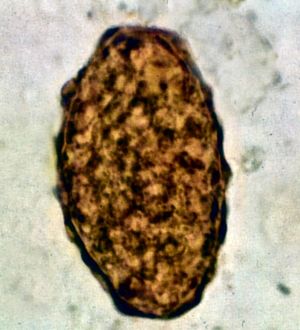

수정된 알은 타원형 또는 둥근 모양이며 길이는 45μm에서 75μm, 폭은 35μm에서 50μm이며 두꺼운 바깥 껍질을 가지고 있다. 수정되지 않은 알은 길이가 88μm에서 94μm, 폭은 44μm이다.[9]